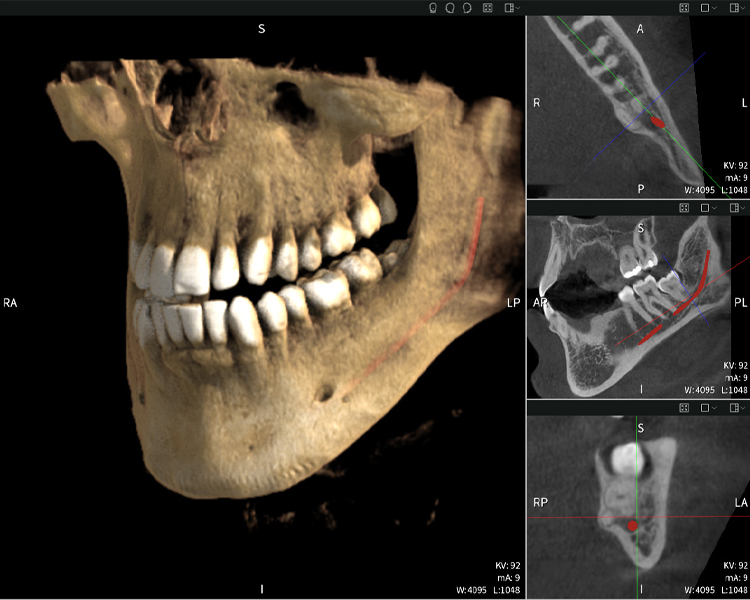

Nachstehend finden Sie einen Fall von Dr. med. dent. Oliver A. Centrella, in dem die CBCT-Aufnahmen mit Seethrough Max entscheidende Informationen zur komplexen Anatomie sowie zur kritischen Beziehung zwischen den Weisheitszähnen und dem Nervus alveolaris inferior lieferten. Bei diesem Fall besteht eine Indikation zur chirurgischen Entfernung der Weisheitszähne.

Abbildung a

- Oben links: Axiale Schnittansicht des linken Unterkiefers (Region 38) mit Darstellung des Nervus alveolaris inferior (rot) in unmittelbarer Nähe zu den Wurzeln des Zahns 38.

- Oben rechts: 3D-Rekonstruktion des gesamten Unterkiefers zur Orientierung. Der rot markierte Nervus alveolaris inferior verdeutlicht seine Lage im Kieferknochen.

- Unten links: Sagittale Ansicht des Unterkiefers (Region 38), die die enge räumliche Beziehung zwischen den Wurzeln und dem Nervenkanal verdeutlicht.

- Unten rechts: Koronale Ansicht des Unterkiefers (Region 38) entscheidend für die Beurteilung der räumlichen Lage der Wurzeln zum Nerven.